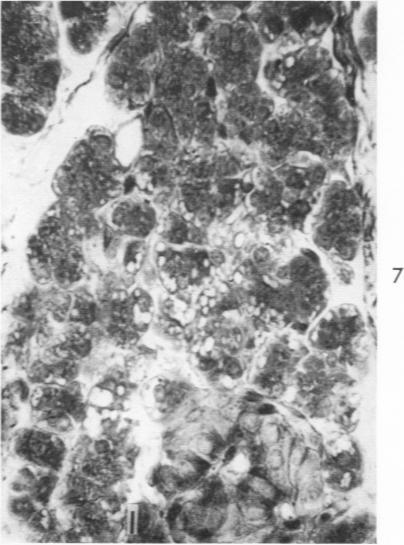

Volk B W, Lazarus S S

Am J Pathol. 1960 Aug;37(2):121-35.